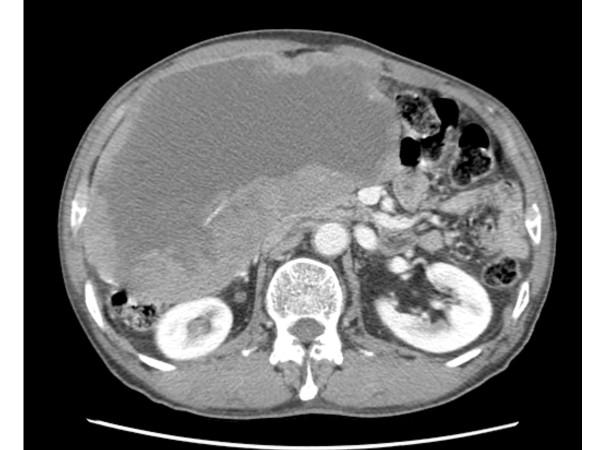

A 71-year-old man was admitted with a one month history of epigastric pain and a palpable mass in the right upper quadrant. An abdominal CT scan revealed a 20 x 19 cm intraabdominal mass with tumor invasion into the peritoneum. Needle biopsy was performed and the results showed spindle shaped tumor cells that were positive for c-KIT. The patient was diagnosed with unresectable GIST. Imatinib 400 mg/day was started. The patient tolerated the first eight weeks of treatment. However, about three months later, the patient developed a grade 4 febrile neutropenia and a grade 3 exfoliative skin rash. The patient recovered from this serious adverse events after discontinuation of imatinib with supportive care. However, the skin lesions recurred whenever the patient received imatinib over 100 mg/day. Therefore, imatinib 100 mg/day was maintained. Despite the low dose imatinib, follow up CT showed a marked partial response without grade 3 or 4 toxicities.

一名 71 岁男性因上腹痛和右上象限可触及肿块一个月入院。腹部 CT 扫描显示 20×19cm 大小的腹腔内肿块,肿瘤侵犯腹膜。进行了针吸活检,结果显示梭形肿瘤细胞 c-KIT 阳性。患者被诊断为不可切除的 GIST。开始给予伊马替尼 400mg/天。患者在前 8 周的治疗中耐受良好。然而,大约 3 个月后,患者出现了 4 级发热性中性粒细胞减少和 3 级剥脱性皮炎。在停用伊马替尼并给予支持治疗后,患者从这些严重的不良反应中恢复。然而,每当患者接受超过 100mg/天的伊马替尼治疗时,皮肤病变都会复发。因此,维持伊马替尼 100mg/天。尽管剂量较低,但随访 CT 显示部分缓解明显,无 3 或 4 级毒性。